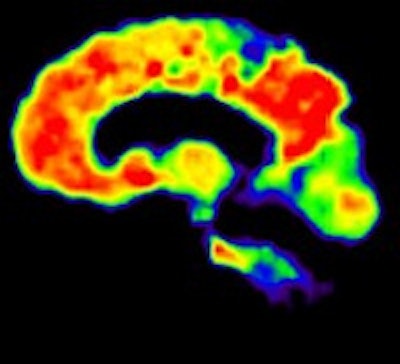

In recent years, both FDG and PiB have become more prominent biomarkers in the diagnosis of several forms of dementia, Ossenkoppele noted. PiB is designed to detect deposits of amyloid plaque in the brain, which have been associated with the onset of Alzheimer's disease. FDG measures metabolic activity of the brain at rest and has been used to distinguish between several forms of dementia.

Researchers then proceeded to the PET scans. First, patients were imaged with PiB for 90 minutes to obtain parametric images of the biomarker binding to potential clusters of amyloid. FDG-PET scans were then conducted 45 to 60 minutes after injection and lasted for 15 minutes. Standardized uptake value (SUV) ratios were calculated throughout the brain.

The resulting PET images were visually assessed by a nuclear medicine physician and reported to the neurologists to determine how the additional information changed their initial clinical diagnoses and their confidence in those interpretations.